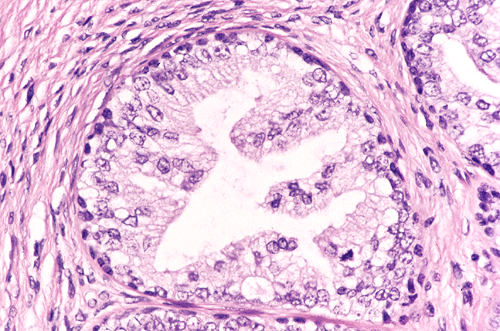

Histologic examination revealed complete replacement of lymph nodes by neoplastic tissue composed of mature mesenchymal, epithelial, and neural components associated with extensive fibrosis. A substantial amount of the tumor was composed of benign fibroblastic growth decorated by nests of epithelium with cyst formation. While most of the epithelial elements are that of intestinal or respiratory type (Panel A, arrow), a few small foci (less than 5%) appeared distinctly different. These foci consisted of small epithelial acini with a lobulo- centric arrangement (Panel A). The acini were composed of two cell types: cuboidal epithelial cells lining the lumens and smaller, more hyperchromatic cells located at the base of the acini. The epithelial cells showed proliferative features such as papillary luminal projections without fibrovascular cores, intraluminal bridging of these projections and mounds of pseudostratified cells (Panel B). These cells had abundant clear and granular cytoplasm. The nuclei were enlarged compared to the stromal cells, had fine chromatin pattern and occasionally had prominent nucleoli (Panel C). High molecular weight cytokeratin (34BE12) was expressed by the cells located at the periphery of these acini as a continuous or interrupted layer (Panel D). No immature teratoma elements or residual seminoma were noted in any of the lymph nodes.

Immunohistochemistry also disclosed strong expression of prostate specific antigen (PSA) and prostate specific acid phosphatase (PSAP) in the glandular elements. Prostatic lineage of these cells was thus confirmed. The histologic and immunohistochemical features of these epithelial cell nests were those of a high grade prostatic intraepithelial neoplasia (PIN). The differential diagnosis in this case included benign and neoplastic prostate tissue as well as other glandular tissues in mature teratoma. The morphology and immunohistochemical features, however, were diagnostic for a high grade PIN. There was no invasive adenocarcinoma of prostate in the metastatic mature teratoma.